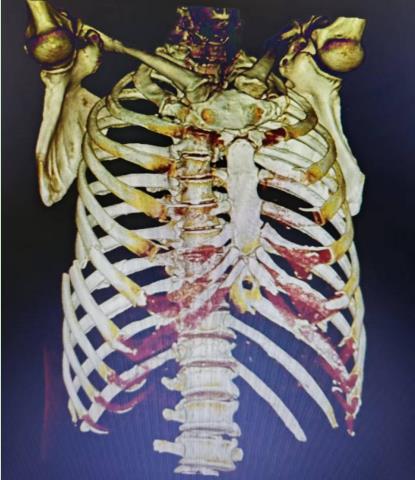

• 骨创伤治疗仪联合胸腔镜下肋骨骨折内固定手术治疗多发肋骨骨折合并血气胸的临床疗效

2025, 31(12):33-42. DOI: 10.12235/E20240685

摘要 (86) HTML (51) PDF 5.26 M (84) 评论 (0) 收藏

摘要:目的 探讨胸腔镜下肋骨骨折内固定术后,辅助给予骨创伤治疗仪,治疗多发肋骨骨折(MRF)合并血气胸的临床疗效及安全性。方法 选取2021年1月-2024年1月该院收治的MRF合并血气胸患者86例,采用随机数表法将患者分为两组,各43例。两组均接受胸腔镜下肋骨骨折内固定手术治疗,对照组于术后给予常规处理,观察组在对照组基础上,接受骨创伤治疗仪辅助治疗。观察两组患者近期和远期疗效。比较两组患者术前、术后3 d、术后7 d和术后14 d的血胸出血量和疼痛视觉模拟法(VAS)评分。比较两组患者术前和术后14 d的凝血功能指标[凝血酶原时间(PT)、活化部分凝血活酶时间(APTT)、凝血酶时间(TT)、纤维蛋白原(FIB)和D-二聚体(D-D)]。比较两组患者术后恢复情况(引流管留置时间、肿胀消退时间、住院时间和骨折愈合时间)和术后并发症发生情况。结果 观察组近期疗效总有效率为97.67%(42/43),明显高于对照组的81.40%(35/43),差异有统计学意义(P < 0.05)。观察组远期疗效总有效率为97.67%(42/43),与对照组的88.37%(38/43)比较,差异无统计学意义(P > 0.05)。术后3、7和14 d,两组患者血胸出血量明显少于术前,且观察组明显少于对照组,两组患者疼痛VAS评分明显低于术前,且观察组明显低于对照组,差异均有统计学意义(P < 0.05)。术后14 d,两组患者PT、APTT和TT明显长于术前,且观察组明显长于对照组,两组患者FIB和D-D明显低于术前,且观察组明显低于对照组,差异均有统计学意义(P < 0.05)。观察组引流管留置时间、肿胀消退时间、住院时间和骨折愈合时间明显短于对照组,差异均有统计学意义(P < 0.05)。观察组术后并发症总发生率为2.33%(1/43),与对照组的11.63%(5/43)比较,差异无统计学意义(P > 0.05)。结论 胸腔镜下肋骨骨折内固定术后辅助给予骨创伤治疗仪治疗,能有效地促进MRF合并血气胸患者胸腔积气和积液的吸收,减轻疼痛程度,改善凝血功能,加快术后机体恢复。值得临床推广应用。